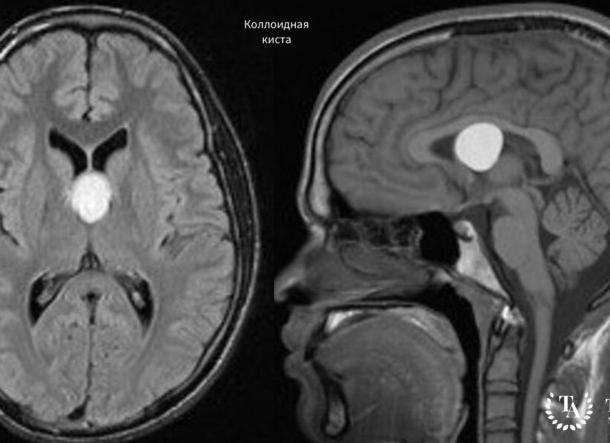

- Коллоидная киста образуется в период формирования головного мозга плода. Долгое время протекает бессимптомно. Увеличение размеров приводит к гидроцефалии и требует нейрохирургического вмешательства.